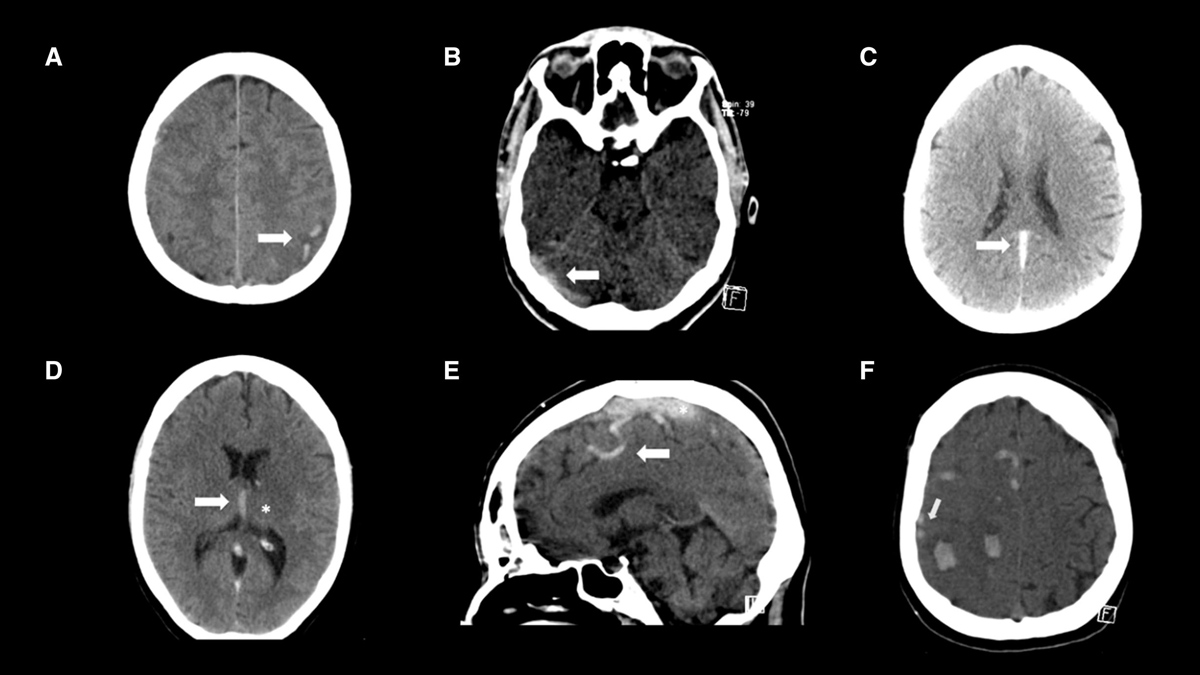

Cerebral Venous Thrombosis is a rare but potentially fatal condition in which a blood clot forms in the venous sinuses of the brain. These sinuses are responsible for draining blood from the brain. When a blockage occurs, it can lead to increased pressure, brain swelling, or haemorrhage, which, in severe cases, can cause permanent brain damage. As per Dr Jaideep Bansal, HOD and Senior Consultant, Neurology Department, Saroj Super Specialty Hospital, women are more susceptible to suffering from Cerebral Venous Thrombosis because they have relatively more hormonal changes.

CVT is considered a rare type of stroke that affects about 5 people per million annually. In pregnant women, the risk increases due to hormonal changes, increased blood volume, and a heightened propensity for clotting during pregnancy and the postpartum period.While CVT in children is rare, newborns are most at risk in their first month of life.